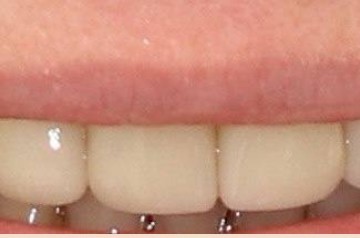

Стоматологическая клиника МИЛА ДЕНТ (MILA DENT)

Протезирование зубов